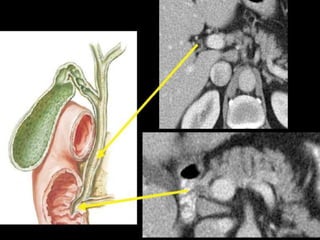

Common bile duct

Gallbladder stones.